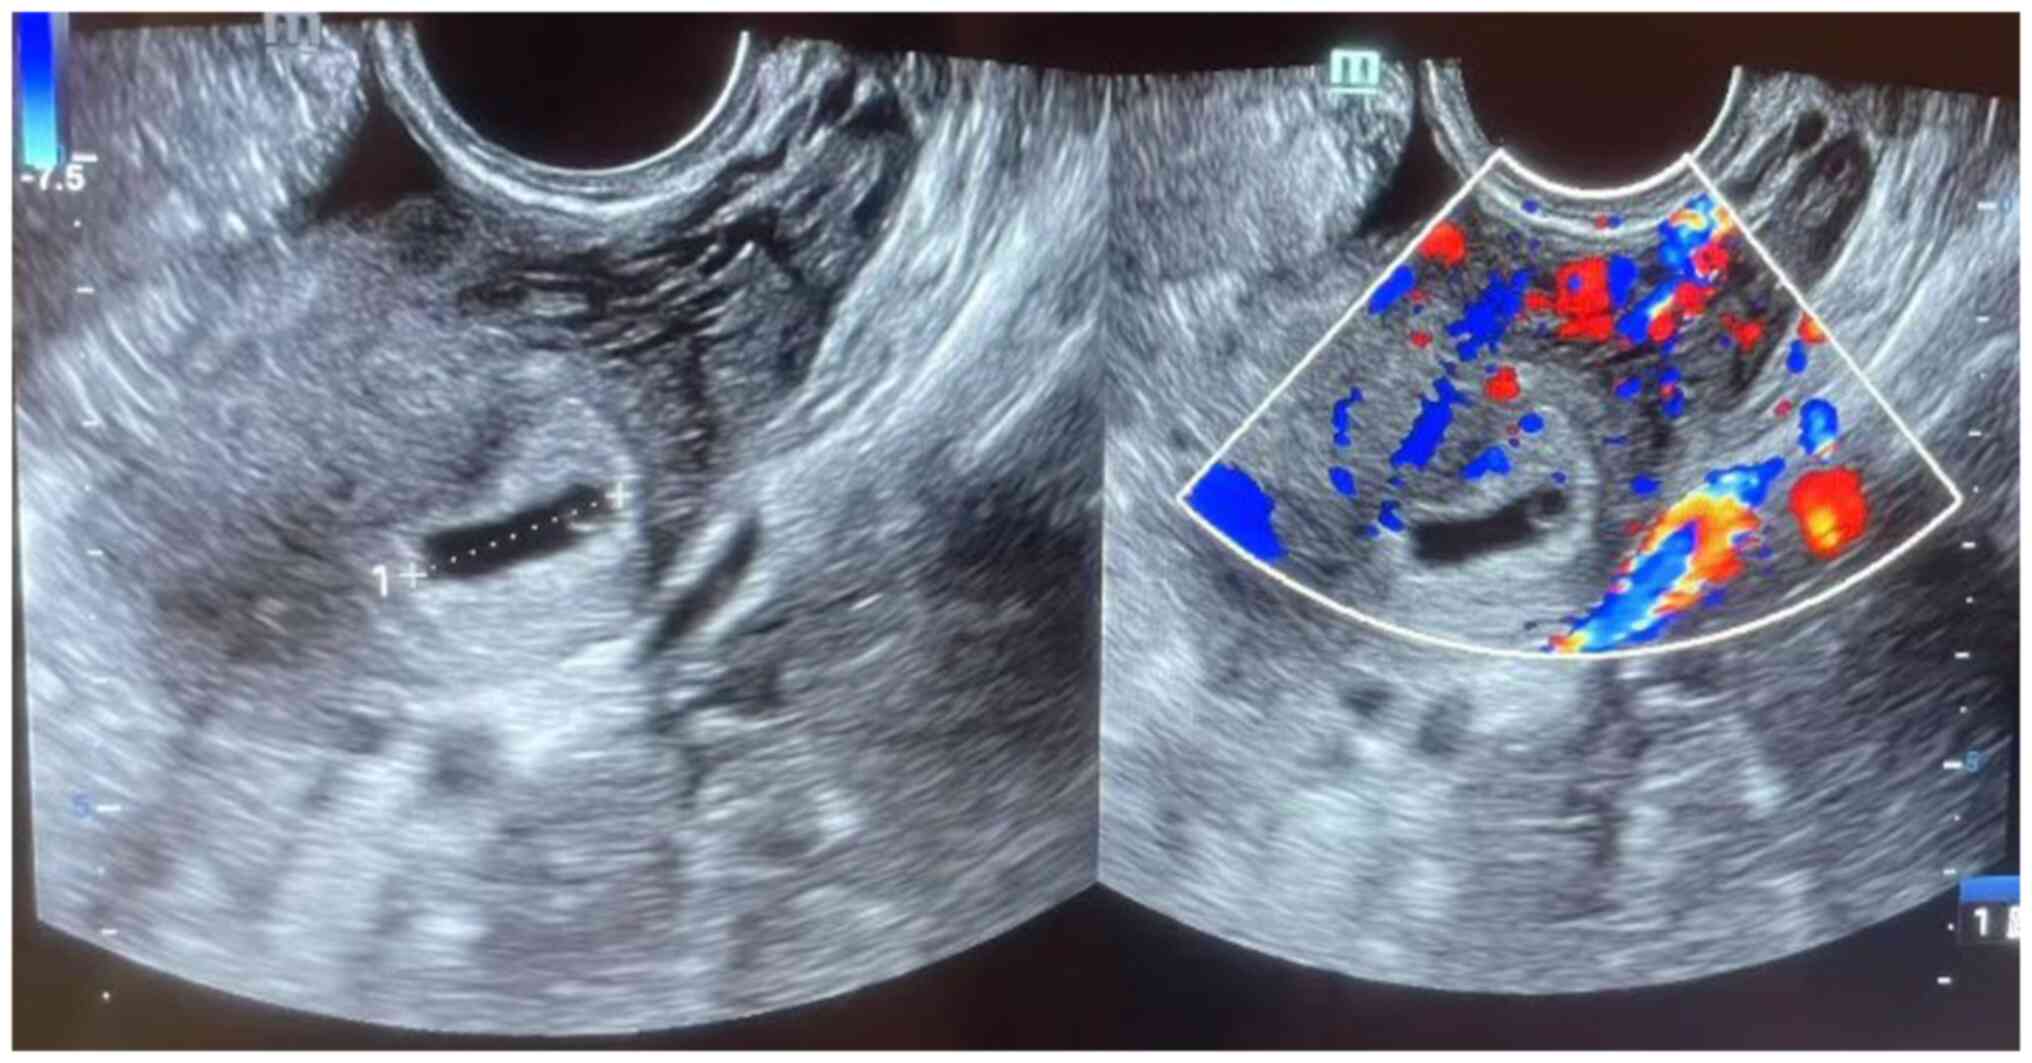

Figure 1

A representative ultrasound of early

pregnancy.